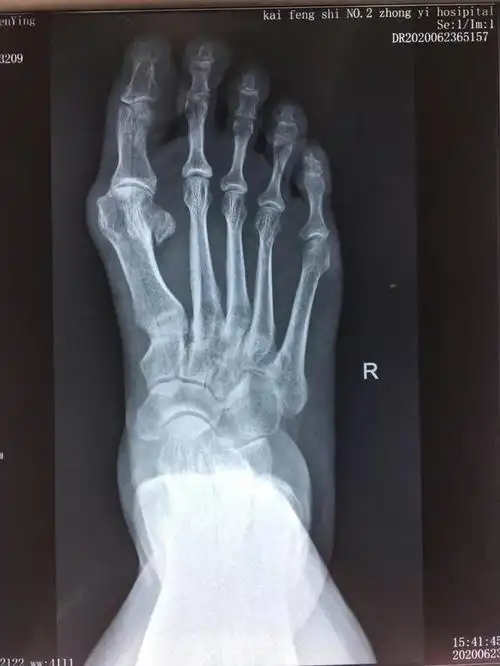

大脚骨片子

负重x线片观察:第一二跖骨间夹角增大明显,第二跖趾关节半脱位.

x光片更直观了解大脚骨 如果单纯去掉凸起能否有效矫正拇外翻呢?